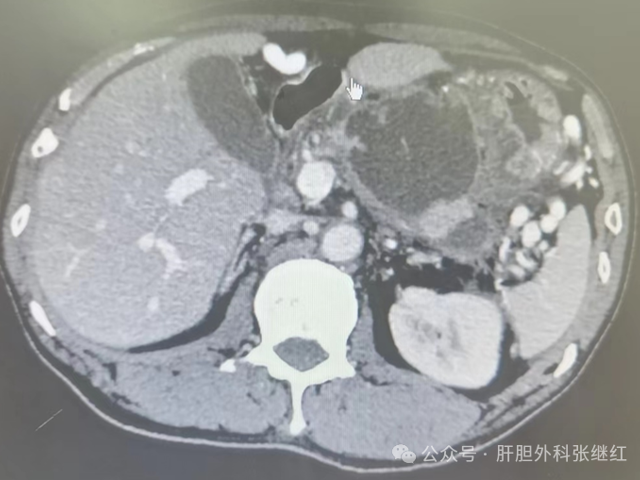

新辅助治疗后前入路右半肝切除术治疗右肝巨大肝癌